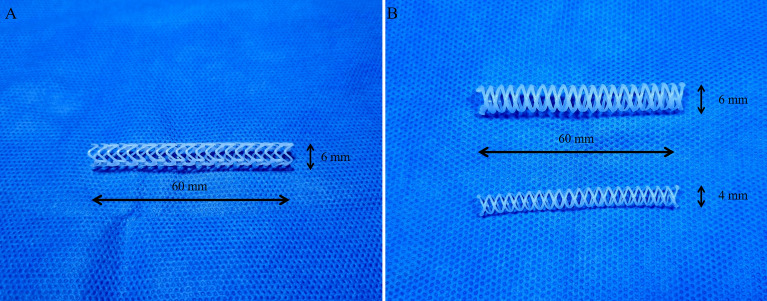

A rotating rod combined with a 3D printing system composed of a driving unit and extrusion unit was used to manufacture biodegradable stents16. The driving unit was operated by a G-code-based robot that consists of two heads moving translationally in the z-direction on the moving parts of x and y. The rotating rod used to print the stent was mounted on a rotating axis. The extrusion unit was composed of a heater and dispenser. The heater heated the material in the syringe to 250 °C. The molten material was extruded using a dispenser capable of providing pneumatic pressure from 0 to 700 kPa. The extrusion volume of the material could be modified using pneumatic pressure and nozzle size. The resolution of the 3D printing system is depending on printing temperature, extrusion pressure, and moving speed. It is possible to print the polymer from 150 μm to 1.5 mm. A rod was used as the substrate to print the tubular structure. Barium-loaded molten PCL was printed on a rotating rod to fabricate a stent with a strut of 500 µm. Our prototype PCL stent was 6 mm in diameter and 6 cm in length, and its shape was capable of loading into the delivery system used for percutaneous biliary intervention (Fig. 1A). However, the surgeon had a difficulty to insert prototype stent into the common bile duct (CBD) due to high flexibility of the stent. Therefore, we changed the design of the stent to make it easier to insert surgically. Considering the variation in CBD size depending on the pig, we made the final version PCL stent with a diameter of 4 mm or 6 mm and a length of 6 cm (Fig. 1B). The PDO (Resomer® X 206 S; CAS 29223-92-5, Sigma-Aldrich, St. Louis, MO, USA) stents for the radial force comparison test were fabricated in the same manner.